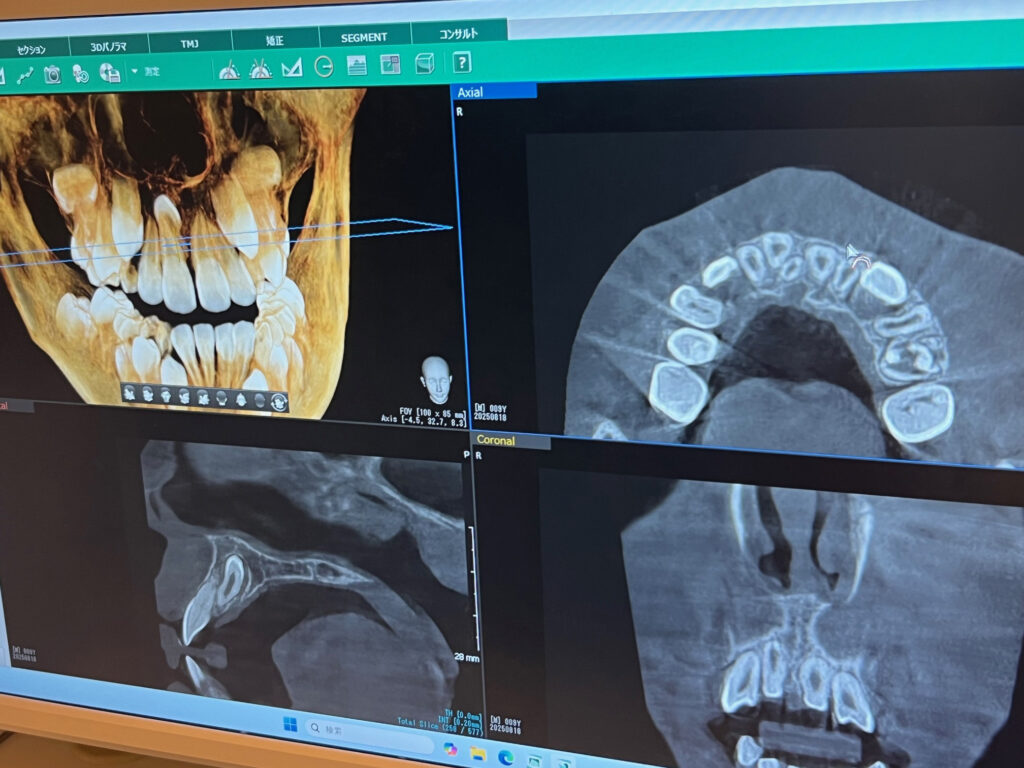

実際、矯正相談の中で、上顎に埋伏した過剰歯が見つかったケースがありました。

しかも、通常とは逆向きに生えている 「逆性」 と呼ばれるタイプで、難抜歯になりやすい位置にありました。